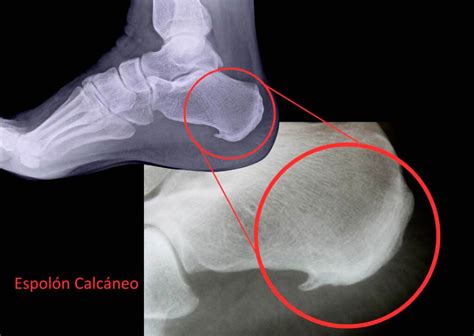

Espolón Calcáneo: ¿Qué es y cómo eliminarlo?